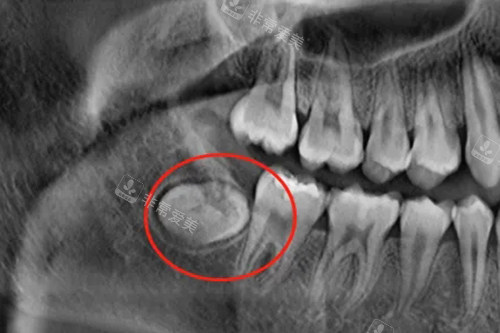

牙龈包裹住智齿

阻生智齿示意图

智齿的位置

阻生智齿埋伏牙片示意图

不同类型的智齿示意图